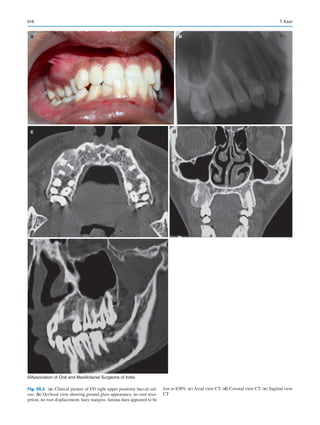

periapical region of teeth

or oral mucosa

perforation

• Procedures on